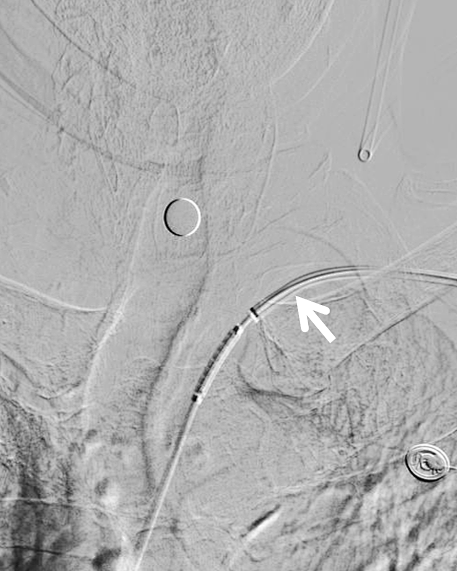

6F NeuronMax 建立良好的支撑【白箭头】,支架顺利对位

动脉长鞘怎么置入健谈卒中|张志勇教授:伐竹取道,另辟蹊径  一例桡动脉入路经NeuronMax长鞘行左侧锁骨下动脉支架置入治疗_https://www.jmylbn.com_新闻资讯_第11张